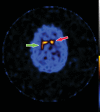

Neurodegenerative diseases are a devastating group of disorders that can be difficult to accurately diagnose. Although these disorders are difficult to manage owing to relatively limited treatment options, an early and correct diagnosis can help with managing symptoms and coping with the later stages of these disease processes. Both anatomic structural imaging and physiologic molecular imaging have evolved to a state in which these neurodegenerative processes can be identified relatively early with high accuracy. To determine the underlying disease, the radiologist should understand the different distributions and pathophysiologic processes involved. High-spatial-resolution MRI allows detection of subtle morphologic changes, as well as potential complications and alternate diagnoses, while molecular imaging allows visualization of altered function or abnormal increased or decreased concentration of disease-specific markers. These methodologies are complementary. Appropriate workup and interpretation of diagnostic studies require an integrated, multimodality, multidisciplinary approach. This article reviews the protocols and findings at MRI and nuclear medicine imaging, including with the use of flurodeoxyglucose, amyloid tracers, and dopaminergic transporter imaging (ioflupane). The pathophysiology of some of the major neurodegenerative processes and their clinical presentations are also reviewed; this information is critical to understand how these imaging modalities work, and it aids in the integration of clinical data to help synthesize a final diagnosis. Radiologists and nuclear medicine physicians aiming to include the evaluation of neurodegenerative diseases in their practice should be aware of and familiar with the multiple imaging modalities available and how using these modalities is essential in the multidisciplinary management of patients with neurodegenerative diseases.©RSNA, 2020.